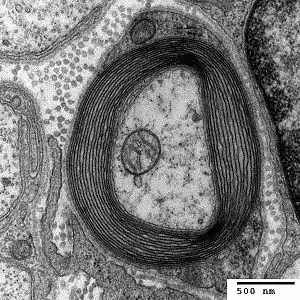

Myelin is considered a defining characteristic of the jawed vertebrates (gnathostomes), though axons are ensheathed by a type of cell, called glial cells, in invertebrates.[16][17] These glial wraps are quite different from vertebrate compact myelin, formed, as indicated above, by concentric wrapping of the myelinating cell process multiple times around the axon. Myelin was first described in 1854 by Rudolf Virchow,[18] although it was over a century later, following the development of electron microscopy, that its glial cell origin and its ultrastructure became apparent.[19]

In terms of total mass, myelin comprises approximately 40% water; the dry mass comprises between 60% and 75% lipid and between 15% and 25% protein. Protein content includes myelin basic protein (MBP),[22] which is abundant in the CNS where it plays a critical, non-redundant role in formation of compact myelin; myelin oligodendrocyte glycoprotein (MOG),[23] which is specific to the CNS; and proteolipid protein (PLP),[24] which is the most abundant protein in CNS myelin, but only a minor component of PNS myelin. In the PNS, myelin protein zero (MPZ or P0) has a similar role to that of PLP in the CNS in that it is involved in holding together the multiple concentric layers of glial cell membrane that constitute the myelin sheath. The primary lipid of myelin is a glycolipid called galactocerebroside. The intertwining hydrocarbon chains of sphingomyelin strengthen the myelin sheath. Cholesterol is an essential lipid component of myelin, without which myelin fails to form.[25]